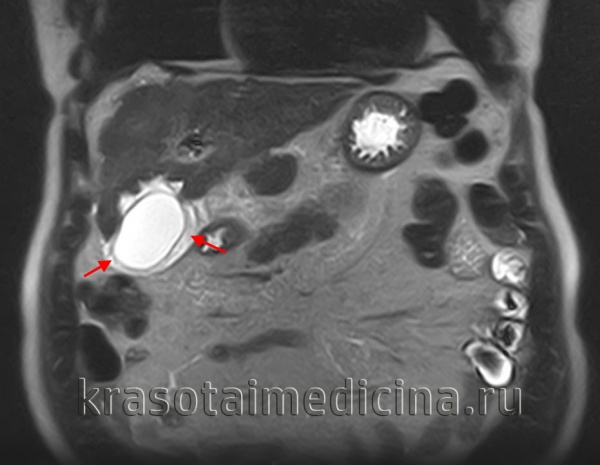

МРТ ОБП. Отек мягких тканей вокруг желчного пузыря.